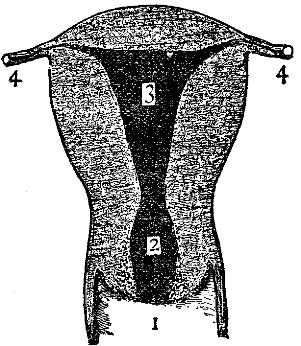

Fig. 2 gives a very good idea of the shape and general structure of this bony framework; while a careful study of Fig. 3 will enable one to form a very correct idea of the relative size and position of the various parts contained in this framework.

Three Parts.—Physicians divide this important organ into three parts,—the fundus, body, and neck. The fundus is all the upper rounded portion; the body all that portion between the fundus and the neck; and the neck all the rounded lower part.

The Cavity of the Uterus.—This is divided into the cavity of the body and the cavity of the neck. By consulting our illustration it is seen that these cavities differ greatly in shape; that of the body being triangular, while that of the neck is barrel-shaped.

By referring again to Fig. 4 it will be seen that the cavity of the body has three openings, one on either side at the top going to the Fallopian tubes, and an opening at the bottom passing into the cavity of the neck. A constriction exists between these two cavities; but after childbirth this is largely done away with, and there is not that marked difference which existed formerly.

Glands in Uterus.—In the mucous membrane lining the uterus are vast numbers of minute glands which secrete mucus. It has been asserted that in the cavity of the neck alone there[Pg 10] are from ten to twelve thousand of these glands. It is in this mucous membrane that such remarkable changes occur each month during menstruation, and still more wonderful changes during pregnancy.

The Ligaments of the Uterus.—By referring to Fig. 5 it will be seen that there are on each side of the uterus flat bands of tissue known as "broad ligaments." These ligaments are attached to the sides of the pelvic cavity, and aid greatly in holding the uterus firmly in place. There are also other ligaments concerned in this same work, although the broad ligaments are most important. The illustration also shows the walls of the vagina cut open, in order that the position of the mouth of the uterus may be easily seen.

| Fig. 4. This illustration shows the cavities in a uterus which has been pregnant. 1, the vagina; 2, cavity of the neck of the uterus; 3, cavity of the body, above which is the fundus of the uterus; 4, Fallopian tubes, extending to the ovaries. | Fig. 5. The female generative organs. 1, the vagina; 2, uterus; 3, broad ligament of left side; 4, a smaller ligament; 5, Fallopian tube; 6, ovary; 7, fringed end of Fallopian tube. |